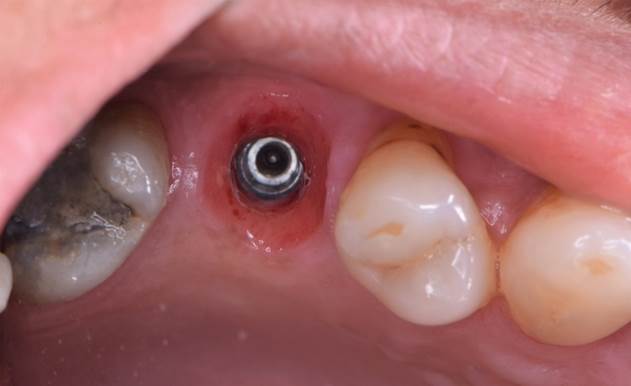

“Prefabricated provisional restorations can serve as custom healing abutments in case of insufficient initial stability for one-day implants. ”

Clinical case: Immediate implant placement using R2GATE Guide & custom healing abutment

- Courtesy of Dr. Sam Omar, Egypt -

Keywords

Dr. Dr. Sam Omar,Digital Guided Surgery,Digital Digital Guided Surgery,Digital ONE-DAY Implant,Maxillary Posterior,#16,Guided surgery,Loading,Flapless,AnyRidge,R2GATE,MEGA ISQ,R2GATE Full surgical kit